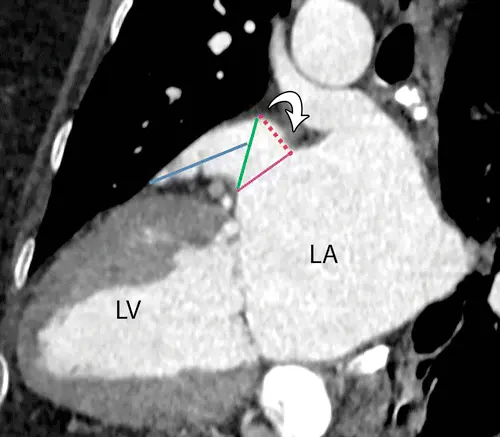

• Caption: Vertical long-axis-view CT image of the left ventricle (LV) shows how the landing zone for a Watchman device is identified at a distance of 10–20 mm (red dotted line) distal to the Coumadin ridge (arrow). The pink line is the LAA ostium. The landing zone diameter is measured in the plane between this point and the point where the left circumflex artery is located (green line). The length of the LAA is also measured on the same image from the landing zone to the tip of the dominant lobe (blue line).